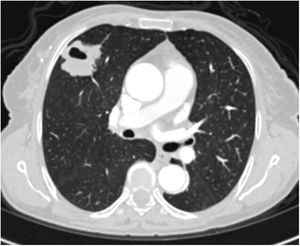

A relationship was identified between the pleura and one or more of the lesions in 25 of the 34 patients diagnosed with PAE (73.5%) (Fig. 1). Following the lesion-pleura relationship, multiple lesions were uniformly scattered throughout the bilateral lung parenchyma in 19 patients (55.8%), seven patients (20.6%) presented with a solitary pulmonary lesion and three patients (8.8%) had multiple unilateral lesions. The diameter of one or more lesions was greater than 3cm in 11 patients (32.4%), only three patients (8.8%) had conglomerated lesions (Fig. 2) and seven patients (20.6%) showed cavitization in some of the lesions. The majority of cavitary mass measured greater than 3cm (Fig. 3). Calcified lesions were recorded in five patients (14.7%), and some of the calcified lesions with lobulated contours had a typical popcorn appearance. Lobulated contours were observed in a significant proportion of non-calcified lesions. Some of the lesions had irregular contours and spicular extensions mimicking malignant processes in five patients (14.7%), while three patients (8.8%) showed multiple micronodular densities with a bilateral uniform dispersion pattern (Fig. 4). The appearance of pulmonary involvement resembled miliary tuberculosis. Parenchymal lesions were accompanied by pleural effusion and parenchymal consolidation in only three patients (8.8%) (Table 1).

Axial thoracic CT scan with lung parenchyma window of a 61-year-old female patient showing a metastatic mass with a diameter greater than 3cm, mimicking a mass lesion located adjacent to the pleura in the right lung with central cavity and peripheral spicular extensions. The patient has been followed for 4 years due to PAE.